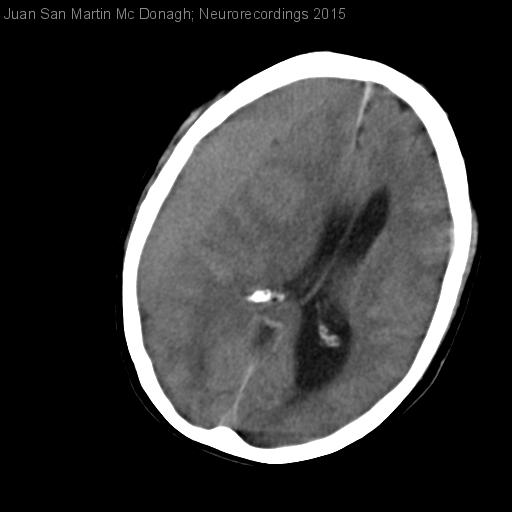

Hombre | 52 años

Diagnóstico final: hematoma subdural subagudo

Neurología: Patología cerebrovascular

Etiología: Trauma | Otros

Juan San Martin Mc Donagh - Hospital General Universitario Gregorio Marañón